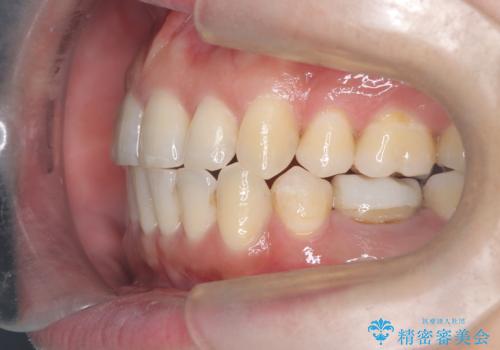

重度の叢生を抜歯矯正で改善|審美ワイヤー矯正+海外出張に伴う中断・再開対応

- 治療計画: 重度の叢生を改善するため、上下左右の小臼歯抜歯を伴う審美ワイヤー矯正を計画しました。抜歯により得られたスペースを利用して歯を整列させ、適切な噛み合わせを目指します。途中、患者様が1年間の海外出張となったため、一時的にワイヤーを外し、保定装置で現状維持を図りました。帰国後に再度審美ワイヤー矯正を再開し、仕上げ調整を行い治療完了を目指します。

重度の叢生により、抜歯を伴う矯正が必要と判断しました。目立ちにくい透明な審美ブラケットを用いたワイヤー矯正を実施しましたが、治療途中での海外出張が決定したため、一度矯正装置を取り外し、保定装置で現状維持を行いました。帰国後に改めて装置を装着し矯正を再開。患者様のライフスタイルに柔軟に対応しながら、最終的には理想的な歯並びと美しい口元を実現しました。